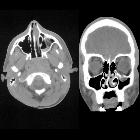

orbital blowout fracture

Orbital blowout fractures occur when there is a fracture of one of the walls of orbit but the orbital rim remains intact. This is typically caused by a direct blow to the central orbit from a fist or ball.

CT

CT is the modality of choice for assessment of the facial skeleton. A full assessment does not require the administration of contrast. Ideally, the acquisition should be performed using the thinnest detector settings, enabling thin-slice reconstructions along three orthogonal planes with a bone algorithm. Additional soft tissue algorithm reconstructions using larger slice thickness and 3D volumetric reconstruction are useful for assessing associated soft tissue injury and gauging facial asymmetry, respectively.

In addition to evaluating the location and extent of fracture(s), other features requiring assessment and reported include:

- presence of intraorbital (usually extraconal) hemorrhage: may result in stretching or compression of the optic nerve

- globe injury/rupture

- extraocular muscle entrapment: suspected if there is an acute change in angle of the muscle

- prolapse of orbital fat